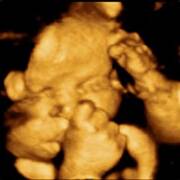

witam wszystkich zaiteresowanych.Ale ten czas leci,jestem już w 32 tygodniu ciąży.Mój synek rośnie(i ja też:) waży już 2kg i rozwija się bez zastrzeżeń pomiomo toksoplazmozy(na szczęście)pozdrawiamy

Jessu jakie piękne Irenko. :):):) Za moich czasów nie było kolorowego Usg az się wzruszyłam.

Moi kochani właśnie trwa 35tydzień,maleńki waży 2500kg a ja o 18kg więcej niż parę miesięcy temu,ale co mi tam jak teraz tak bardzo kochamy jeść:)najważniejsze że synek rośnie zdrowo! nie mogę się już doczekać aż wkleję tu jego foto w realu a puki co muszę wam pochwalić się jak maleńki cycka paluszka w brzuszku:D

Witam wszyskich.Na tę wielkanoc dostałam najcudowniejszy prezent jaki tylko można sobie wymarzyć:)W wielki czwartek przeszedł na świat przez cesarskie cięcie mój ukochany synek Kuba 56cm i 3640kg, 10pkt.dołanczam też zdjęcie bo przeciesz muszę się pochwalić takim przepięknyn prezentem.w czwartek odbieram wyniki na obecność tokso trzymajcie kciuki